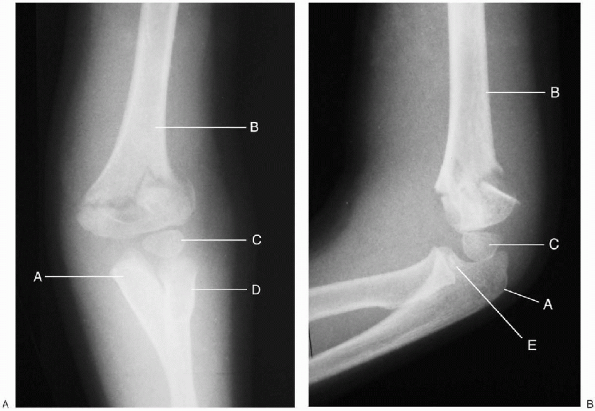

FIGURE 12-2. Type II extension supracondylar humerus fracture (left elbow). A: Anterior-posterior. B: Lateral. A, ulna; B, humerus; C, capitellar epiphysis; D, radius; E, radial head.